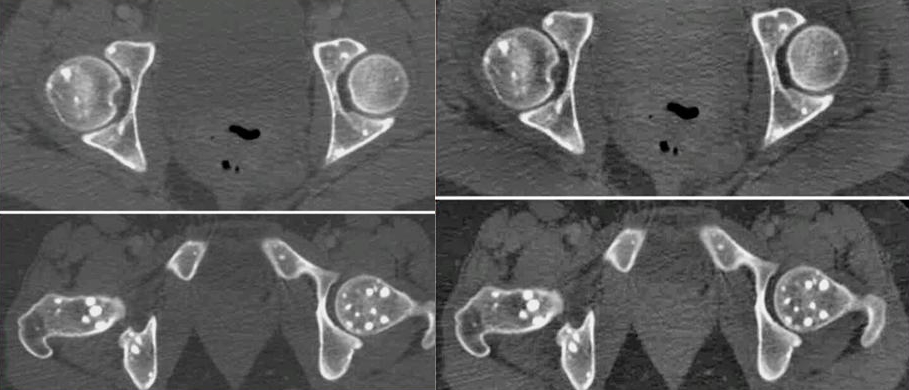

Патология проявляется в виде множества уплотнений, которые обычно располагаются симметрично. Для точного понимания проблемы необходимо изучить рентгеновский снимок. Это заболевание встречается крайне редко, зарегистрировано всего около 100 случаев. Оно является врожденным. Уплотнения в костях имеют овальную форму и могут достигать размеров от 2 до 10 мм.

Каждая форма имеет свои уникальные характеристики. На рентгенограмме внешний вид костей изменяется: они становятся крапчатыми с множеством мелких уплотнений на округлых участках. По особенностям рисунка можно различить пятнистую и полосатую остеопойкилию. В первом случае формируются овальные уплотнения, во втором — продолговатые. Изменение формы очагов поражения указывает на прогрессирование заболевания. При смешанной форме на рентгенограмме видны уплотнения различных размеров и форм, однако такая форма встречается крайне редко.

Для установления точного диагноза проводится рентгенологическое исследование, которое позволяет выявить изменения в костной структуре. Поскольку заболевание не затрагивает состав крови, лабораторные анализы нецелесообразны. Результаты анализа крови и других жидкостей организма будут в пределах нормы.

На рентгеновских снимках оцениваются форма и размеры пораженных костей. При остеопойкилии внешние изменения костных тканей отсутствуют. Уплотнения формируются внутри структуры, не влияя на контуры костей. Процесс развития тканей протекает нормально, без задержек формирования или других патологий, характерных для остеопойкилии. В редких случаях с образованием очагов поражения в костях может развиваться кожное заболевание, известное как чечевицеподобный фиброз.

Кроме основного метода диагностики может быть рекомендовано дополнительное обследование. Оно включает уточнение количества, размеров и расположения очагов поражения костей. Для этих целей назначаются компьютерная или магнитно-резонансная томография.

Очаги поражения чаще всего локализуются в костях таза, запястьев и стоп. Также часто затрагиваются плечи, предплечья, голеностопные суставы и позвонки в некоторых отделах позвоночника (крестцовом и поясничном). Череп и ребра менее подвержены образованию патологий, а ключицы остаются совершенно непораженными.